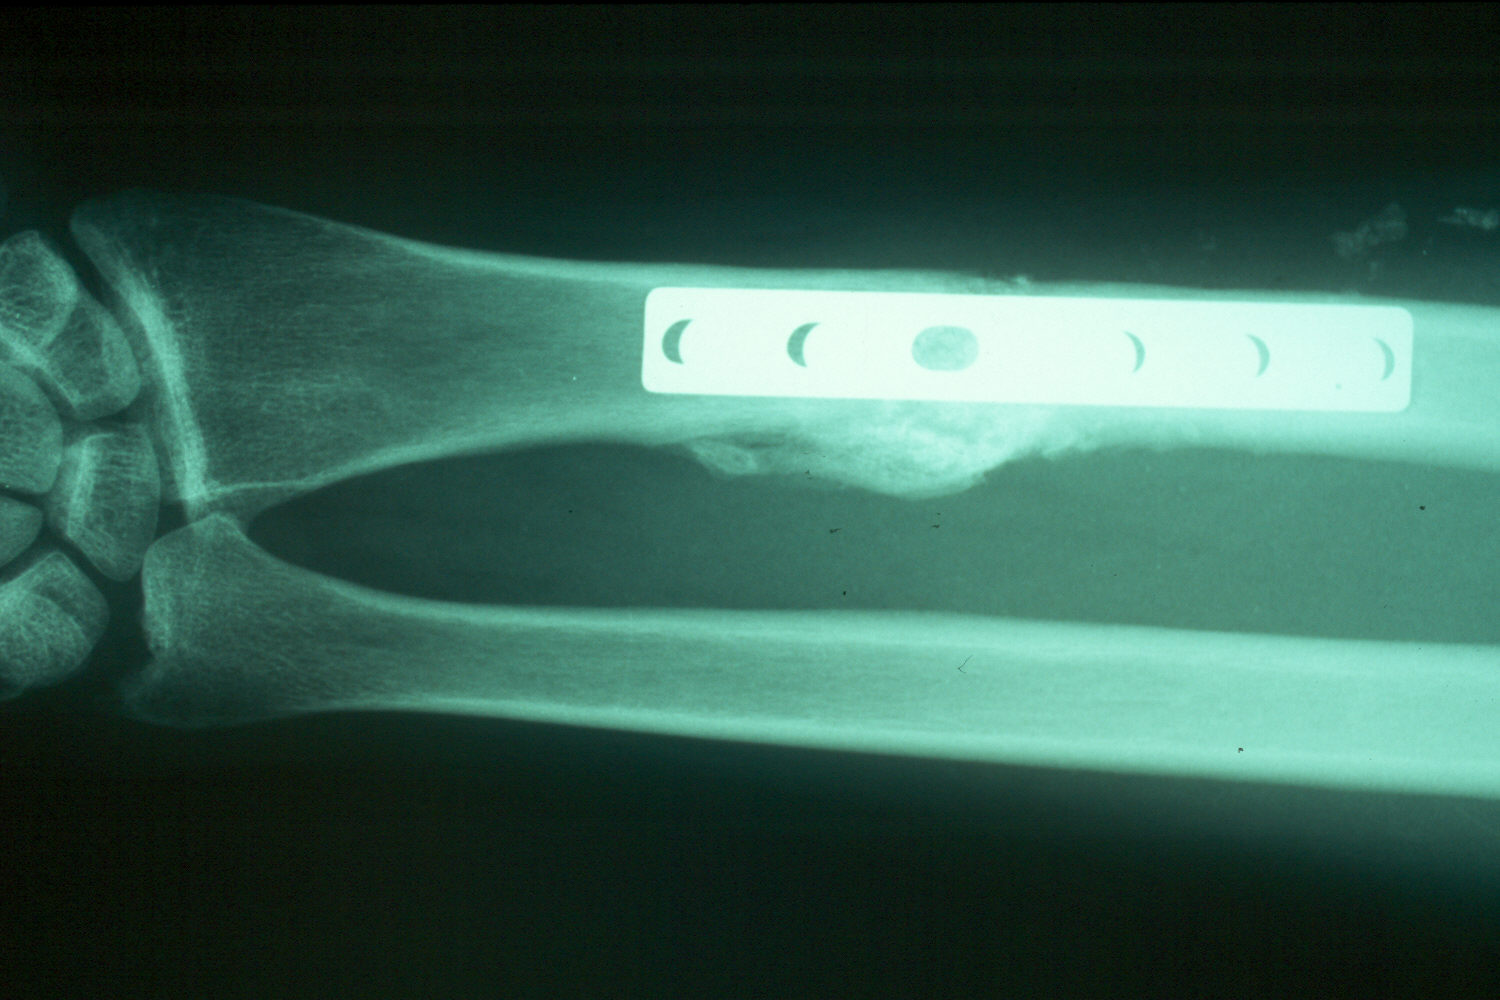

The patient was treated elsewhere with open reduction and internal fixation, but had inadequate restoration of radial length. The patient was troubled by stiffness and pain from distal radioulnar joint incongruity and ulnocarpal abutment syndrome.

Ulnar shortening osteotomy with compression plate fixation restored satisfactory alignment.  The patient had exuberant periosteal bone growth around the side of osteotomy, but did not have evidence of delayed healing, other hardware problems, and had an excellent clinical result in terms of pain relief and recovery of motion.